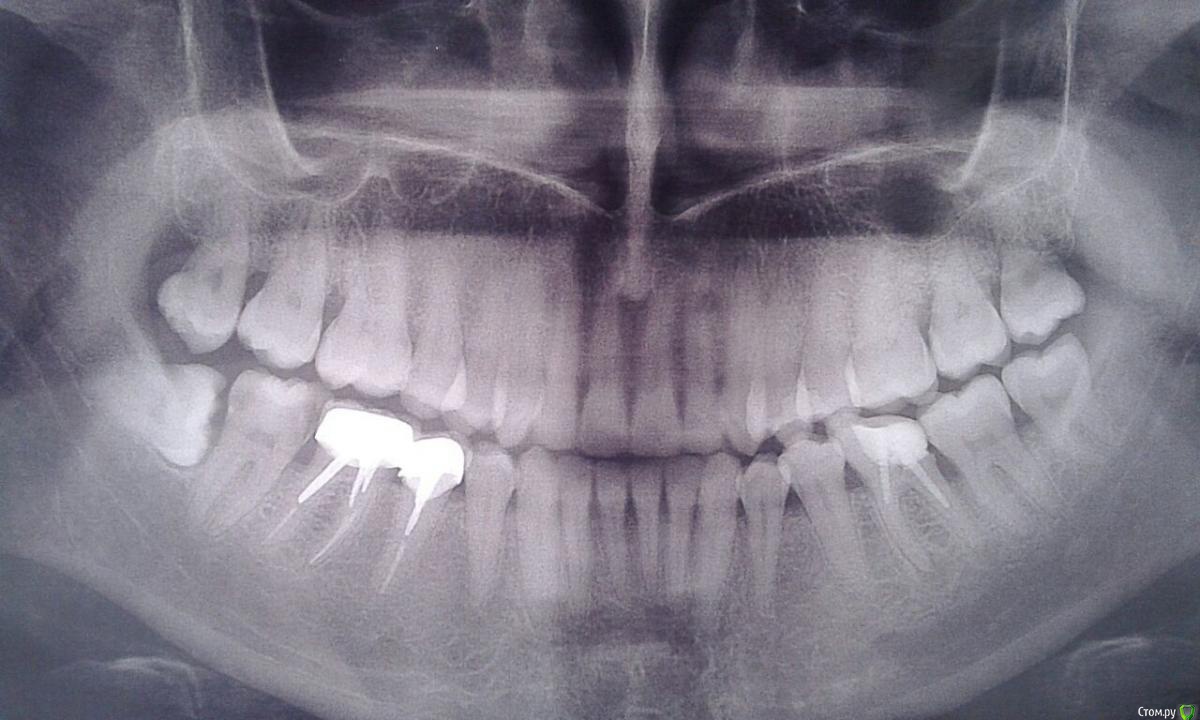

Дентальная галерея: ретинированный зуб клык и его лечение

Раздел: Компас решений